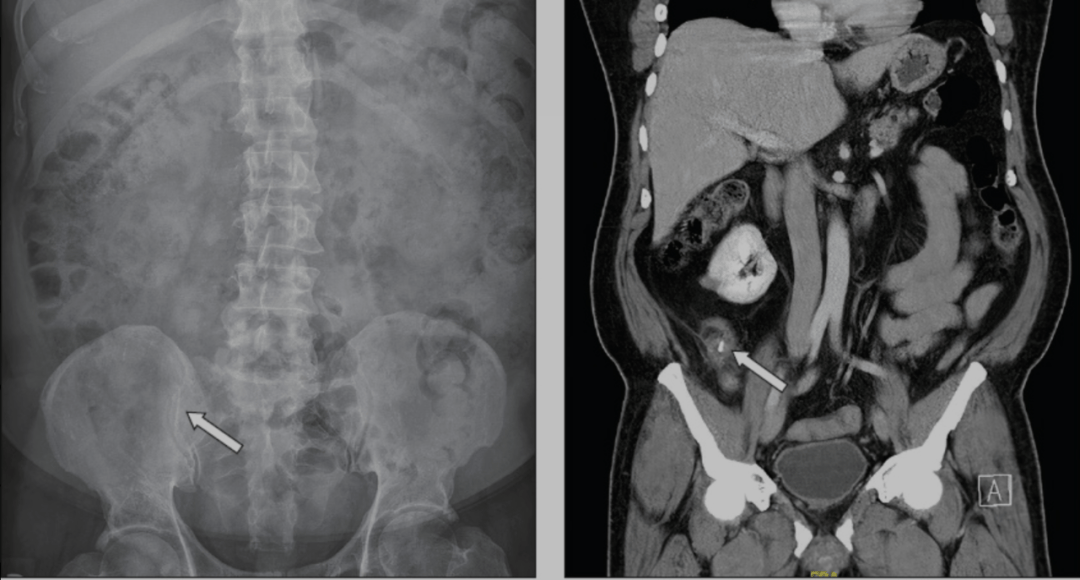

腹部X光片未见异常。

腹部CT显示肝脏IV段有一处边缘强化的不规则低密度灶,大小约5.6×7.5×7.7 cm,与肝脓肿相符。同时,在IV B段肝脏下缘可见一条高密度线状异物,贯穿肝组织,长度约2.5 cm。胆囊形态无异常。胰腺、脾脏、肾上腺和双肾均正常。影像学提示:这是由于肝内异物引起的脓肿。

随后为患者行剖腹探查术。脓肿被引流,同时取出了一根长约2.5 cm的鱼刺。术中偶然发现大网膜与十二指肠区胆囊及肝IV B段之间有粘连,遂予以松解。胆囊壁较厚,遂同时行胆囊切除术。